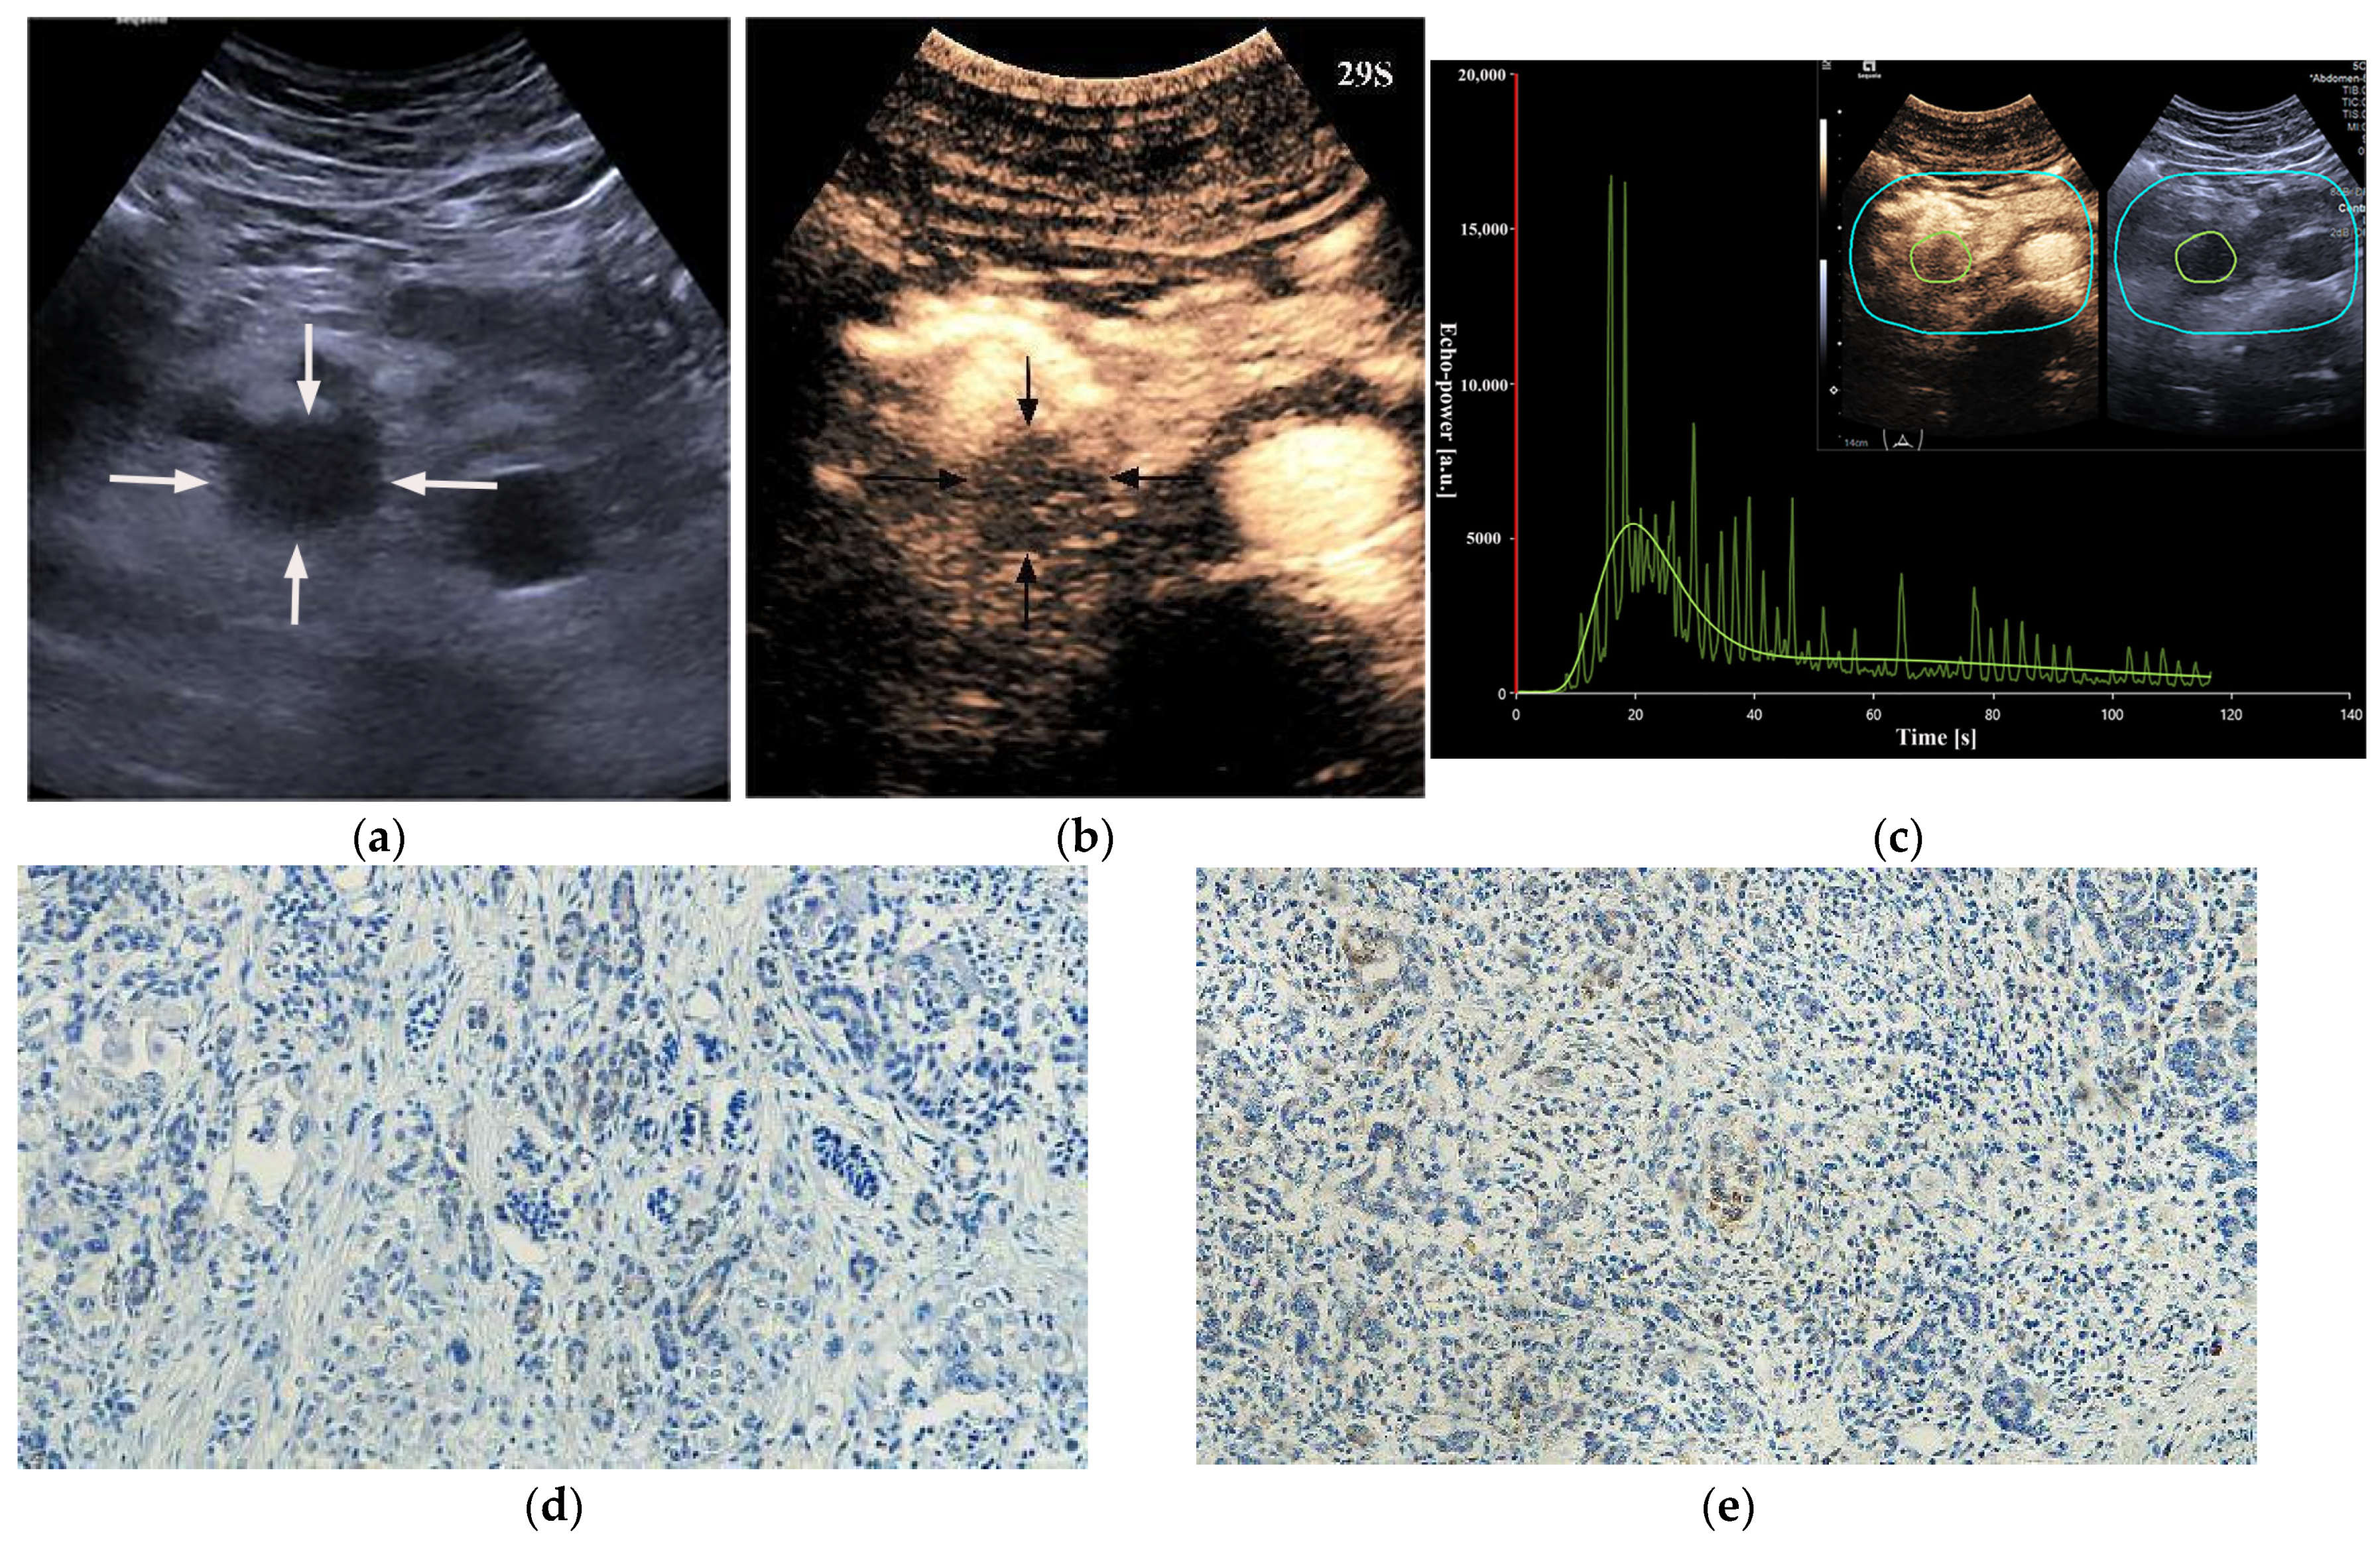

| Completeness of enhancement | ||||||

| Complete enhancement | 35 (68.6%) | 17 (33.3%) | 0.001 | 34 (66.7%) | 18 (35.3%) | 0.003 |

| Incomplete enhancement (enhancement > 50%) | 13 (25.5%) | 22 (43.1%) | 14 (27.5%) | 21 (41.2%) | ||

| Incomplete enhancement (enhancement ≤ 50%) | 3 (5.9%) | 12 (23.5%) | 3 (5.8%) | 12 (23.5%) | ||

| PED | ||||||

| Iso-enhancement | 9 (17.6%) | 19 (37.3%) | 0.027 | 8 (15.7%) | 20 (39.2%) | 0.008 |

| Hypo-enhancement | 42 (82.4%) | 32 (62.7%) | 43 (84.3%) | 31 (60.8%) | ||

| RT [s] | 8.0 (6.7–10.4) | 7.0 (6.2–8.7) | 0.154 | 8.0 (6.7–12.1) | 7.2 (6.0–9.7) | 0.067 |

| TTP [s] | 12.1 (9.7–16.0) | 11.3 (8.8–14.5) | 0.265 | 12.8 (9.8–15.9) | 11.2 (8.7–13.3) | 0.076 |

| PE [a.u.] | 10,693.4 (6566.8–20,600.4) | 16,173.8 (9381.0–27,237.6) | 0.024 | 10,125.9 (7037.8–18,662.1) | 15,939.4 (8939.2–27,388.2) | 0.018 |

| WIR [a.u.] | 1830.6 (868.4–4287.2) | 3607.1 (1973.7–5895.6) | 0.015 | 1898.3 (913.5–3844.3) | 3882.5 (1967.1–6205.7) | 0.002 |

| WiAUC [a.u.] | 57,775.0 (31,068.1–98,571.4) | 80,406.4 (45,124.3–123,632.3) | 0.169 | 57,933.7 (35,078.5–98,126.3) | 78,038.4 (43,797.8–133,500.0) | 0.334 |